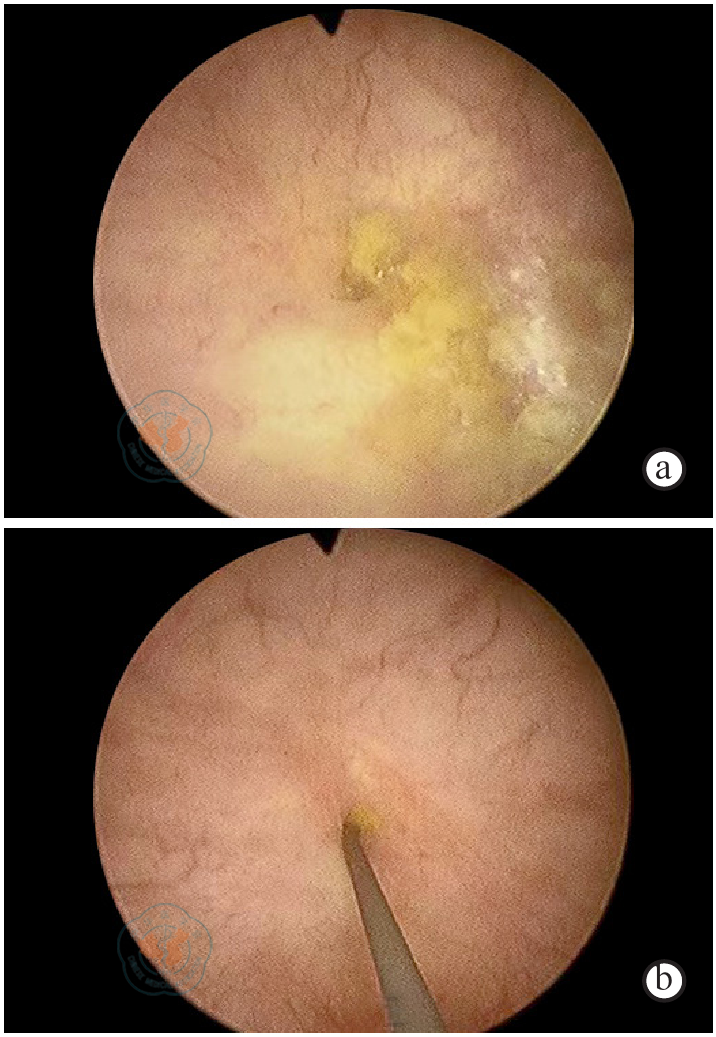

图2 盲肠膀胱瘘患者膀胱镜检查结果注:镜下见膀胱内粪渣及黄绿色絮状物(a),膀胱右侧室见一大小约5 mm瘘口,瘘口可见粪便附着(b)